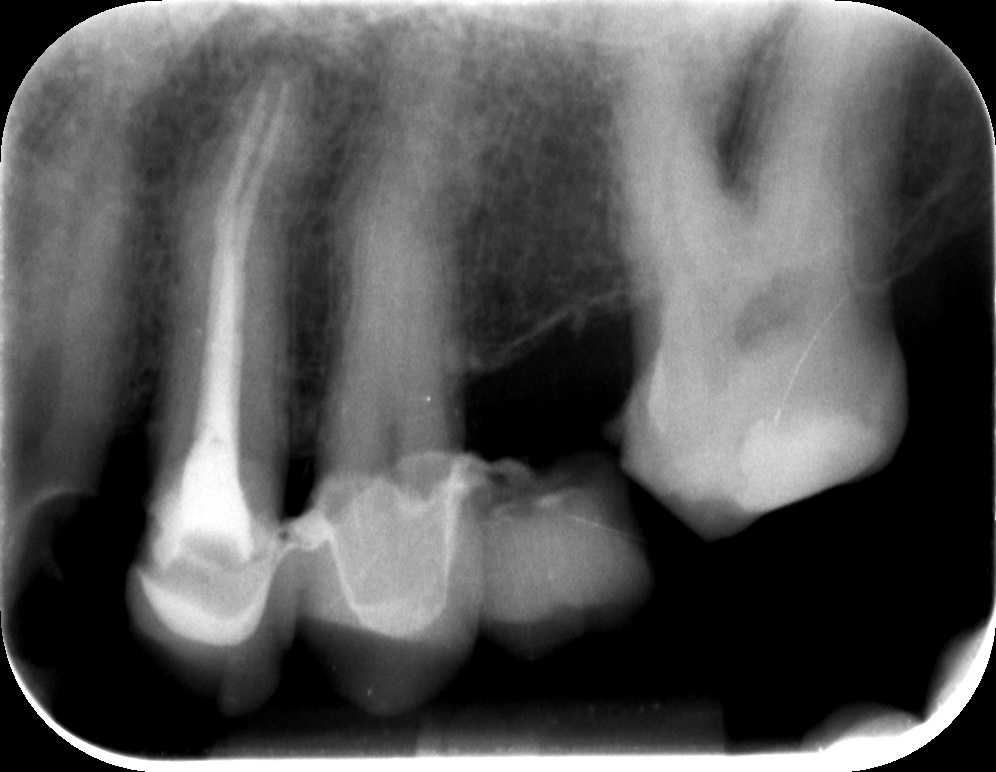

A második alkalommal a csatornák újabb fertőtlenítésére, tisztítására került sor. Ezek után elkészült az új gyökértömés, melyhez ismét igénybe vettük a mikroszkóp segítségét. A fog panaszmentessé vált, így megmenekült attól, hogy el kelljen távolítani! Egy 3 hónapos kontrollfelvétel után már elkészíthető az új fogpótlás, hogy a páciens mosolya újra a régi legyen!

mikroszkópos gyökérkezelés, elkészül az új gyökértömés